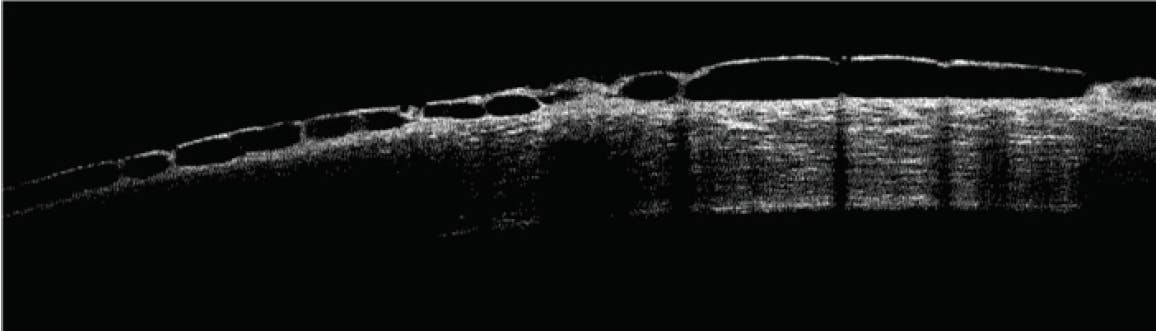

A rarer side effect of netarsudil is reticular bullous epithelial edema, also referred to as corneal honeycombing (Figure 2). In a case series, patients developed reduced visual acuity, inferior bullous keratopathy, stromal edema, and mild anterior chamber inflammation 2 to 4 weeks after starting therapy with netarsudil.21 Significant edema was concentrated under the corneal epithelium. This side effect usually manifested in patients who had predisposing risk factors for developing corneal edema and/or inflammation (eg, history of pseudophakic bullous keratopathy, glaucoma drainage device implantation, etc.). Clinicians should therefore consider these factors before prescribing netarsudil. The edema generally resolved after drug cessation, but the visual acuity decline was permanent.

Figure 2. OCT scan of a cornea with reticular bullous epithelial edema.

Courtesy of Robert Schultz, MD